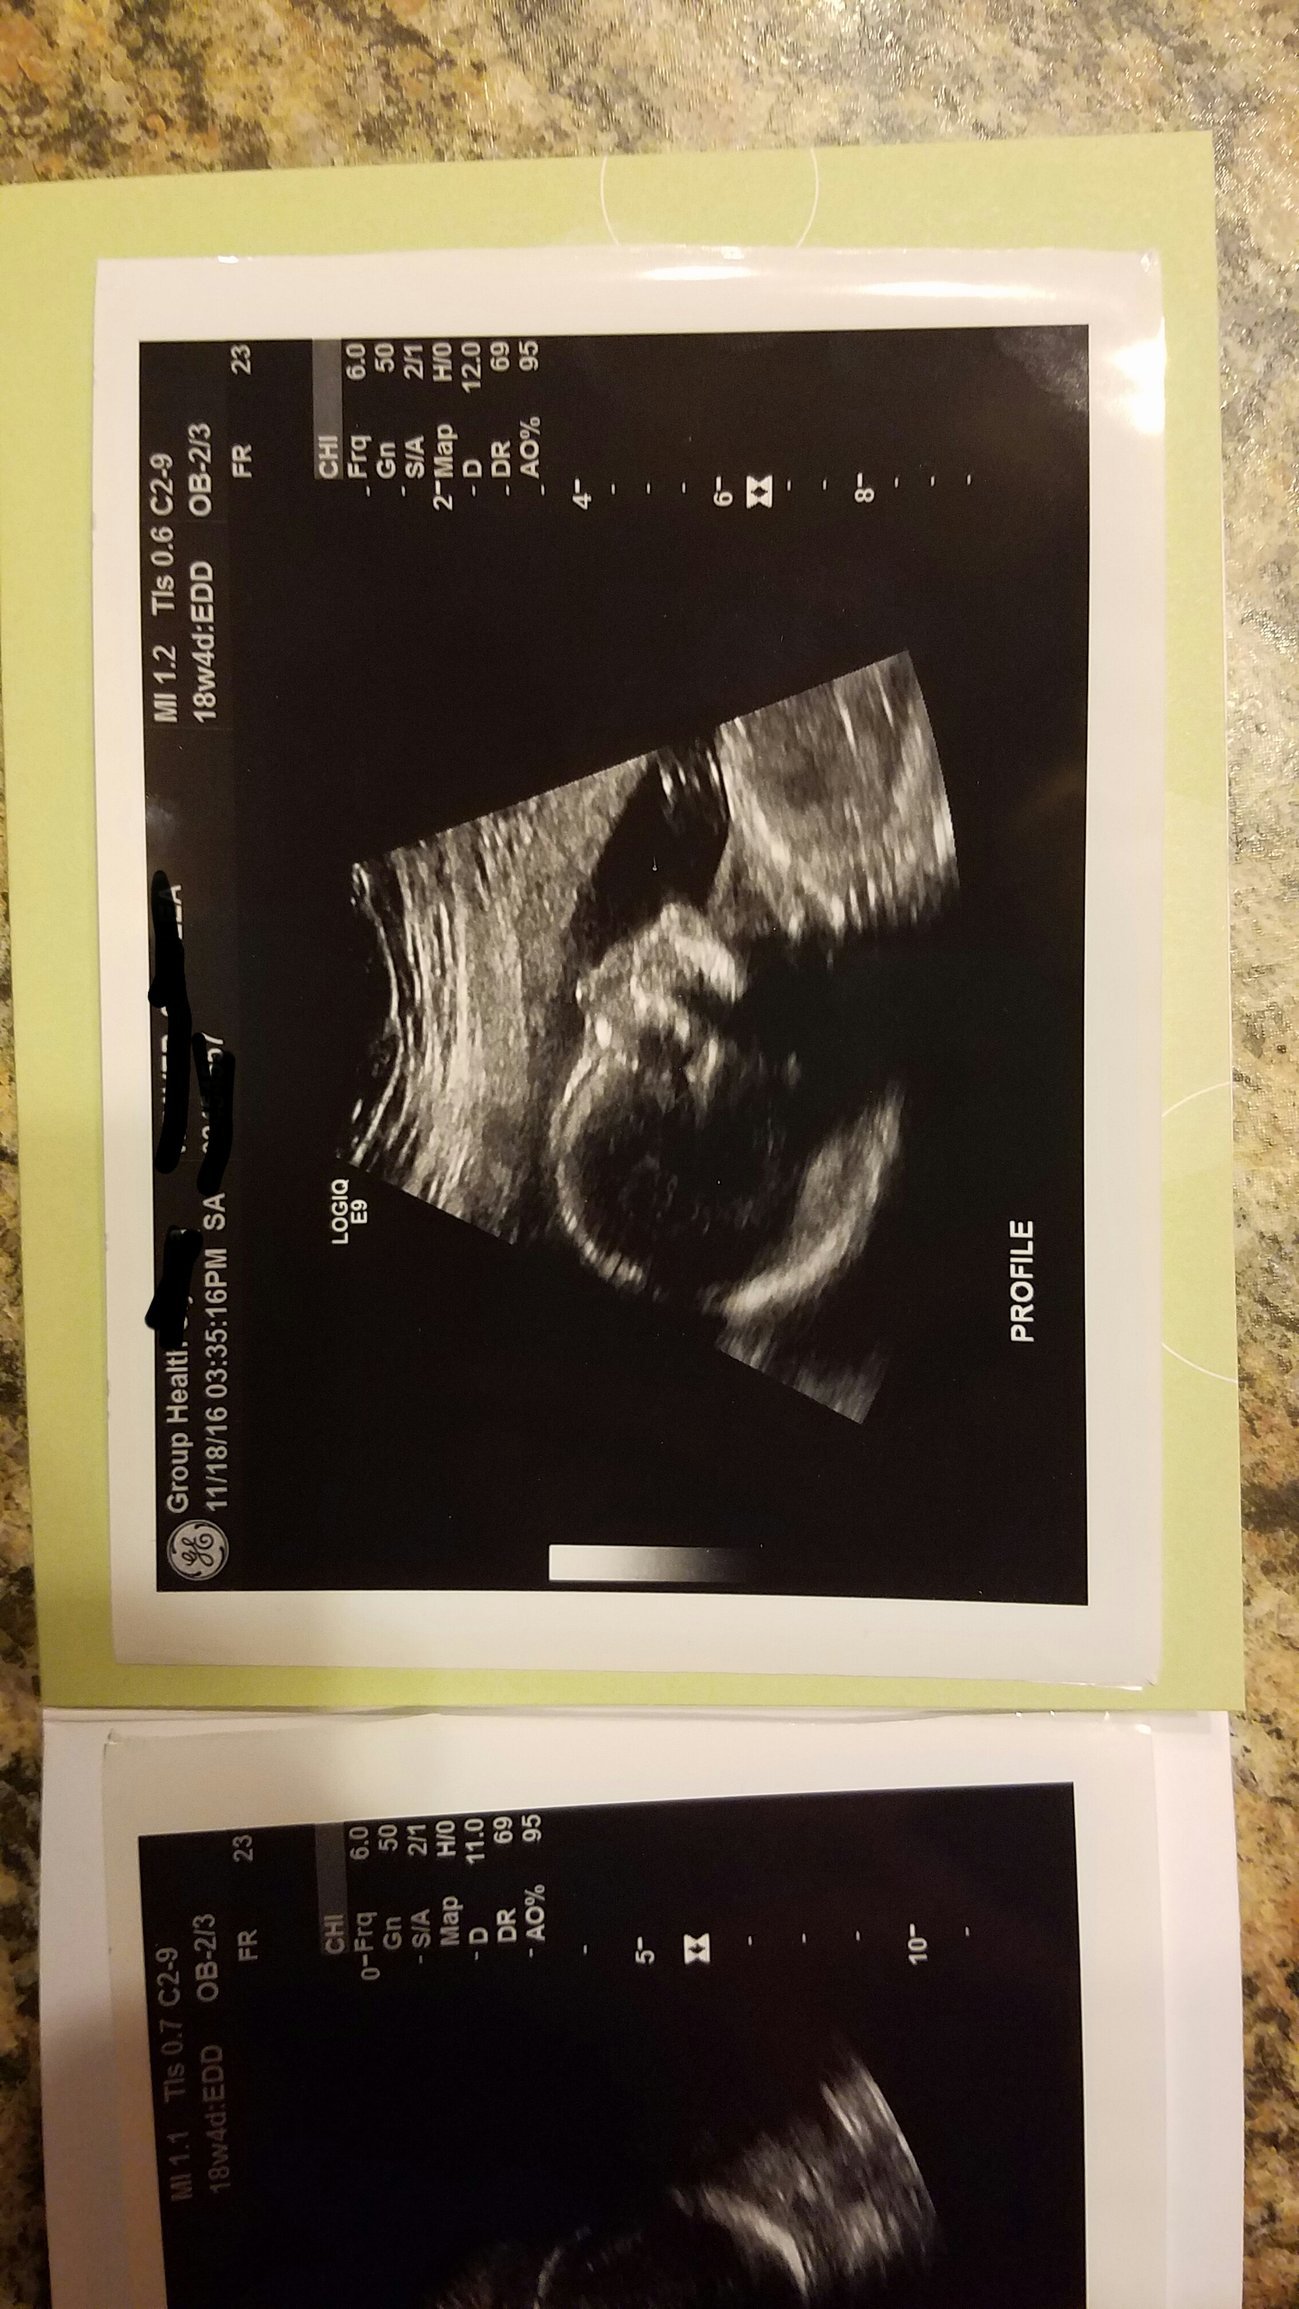

Anatomy scan at 19 weeks, 1 day. It's another obvious little boy! Placenta is posterior (good news having had a previous section), baby looks good. He was very cooperative. 3D was an unexpected little treat!